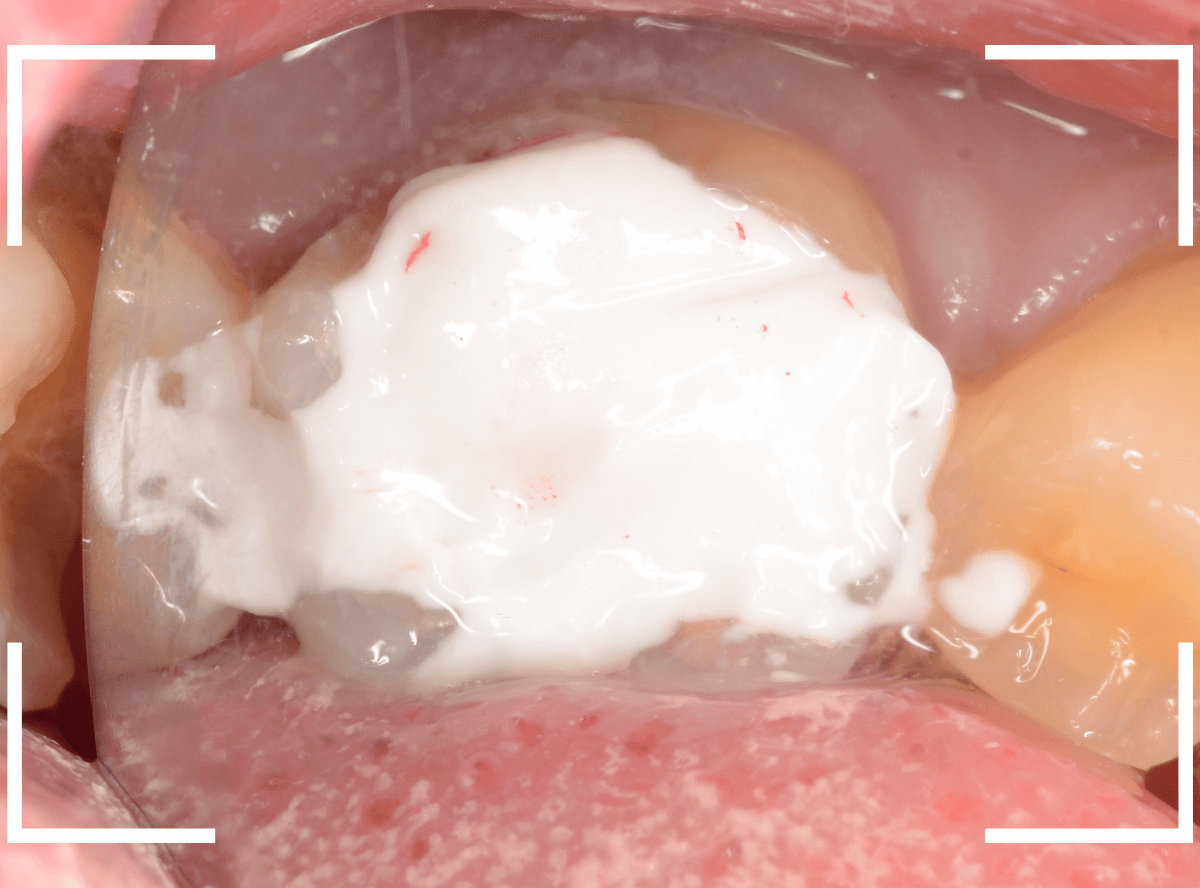

レジンを外しながら、虫歯を確認します。

慎重にレジンを除去しましたが、途中で露髄(神経が露出する事)しました。

歯の神経の中には、血管も含まれているので、神経が露出すると、このように出血します。

「しみる、痛い」などの明確な強い症状がある場合、このような状況の事が多いです。

今回は出血量が多く、神経を除去する治療(抜髄)の可能性が高いとも感じましたが、できる限り神経を保存する方法を取ることにしました。

神経を保護するお薬をつめて蓋をしてしばらく経過観察します。

神経を除去すると、治療期間が長引くうえに、歯の寿命がとても短くなってしまいます。

できるだけ歯の神経を残すためには、症状が出てからの歯科受診ではなく、定期的なメンテンナンス受診を続けるようにしてください。